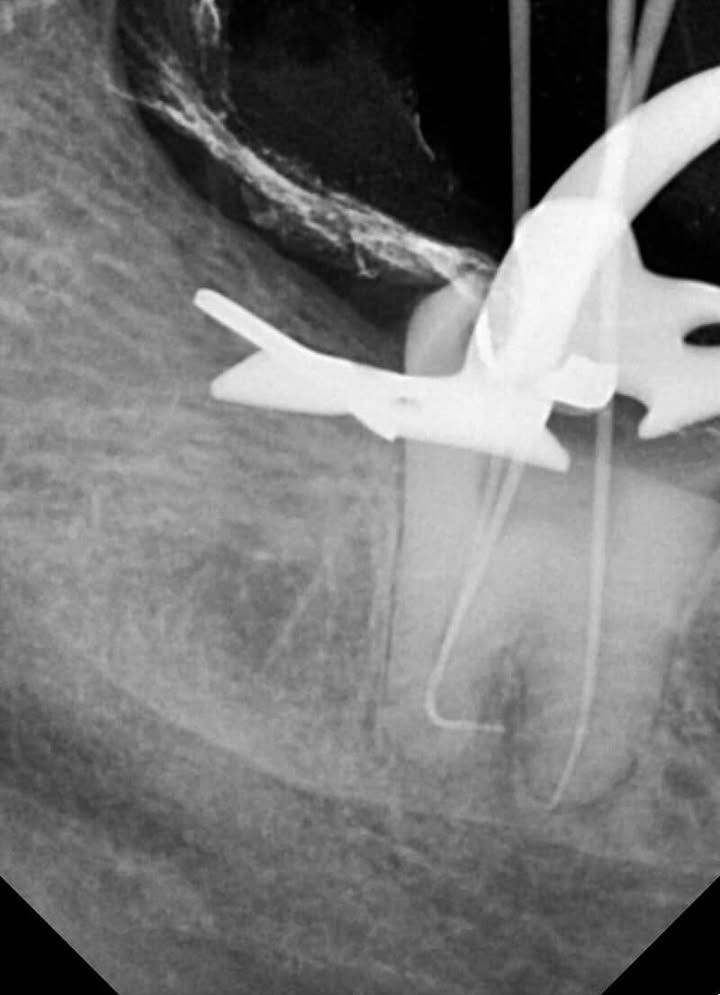

Manual scouting was carried out with pre-curved hand files up to size 15. When apical blockage was encountered, patency was carefully searched for after appropriate pre-curving of both manual and rotary files. - Final Canal Preparation

Final shaping of the canals was safely completed using EZ Shaper Pro (EZ2) files. Due to the extreme curvatures, enlargement was kept conservative. - Obturation

- Pre-curve is Key: When apical blockage is encountered without achieving patency, it is essential to carefully search for patency after appropriate pre-curving of both manual and rotary files.

- Less is More: Excessive enlargement is not recommended in cases with extremely severe curvatures.